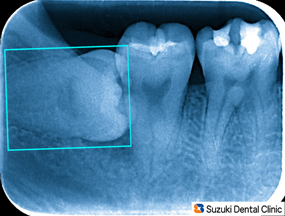

難しい抜歯

コラム「難しい抜歯」の画像